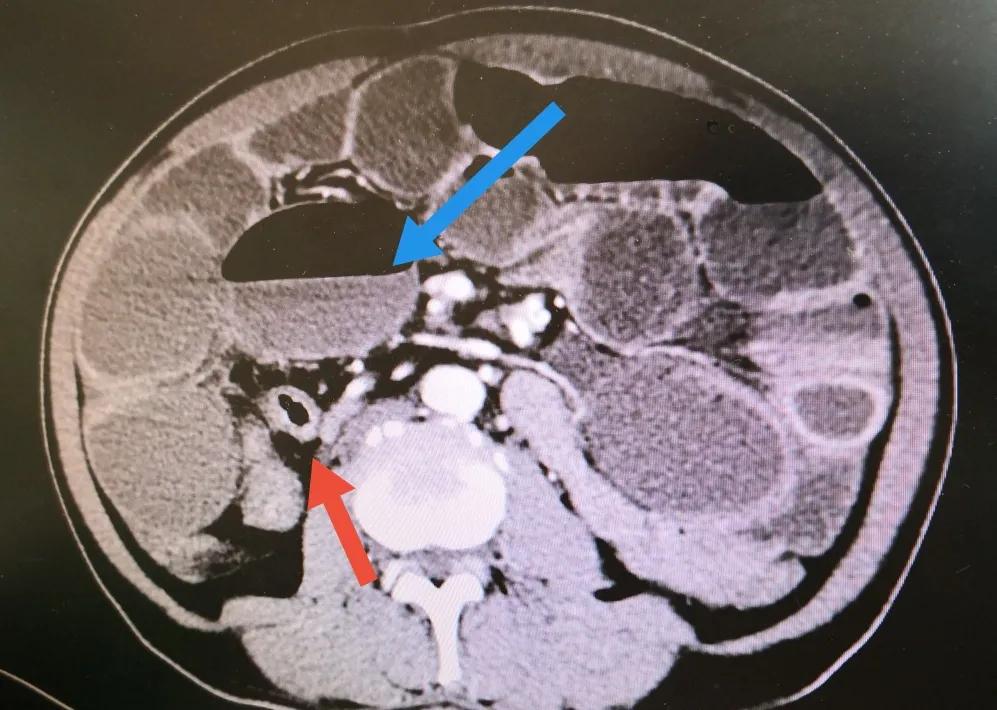

粉红色箭头所示为回盲部肿瘤,已侵犯回肠未端导致全小肠梗阻

蓝色箭头为小肠梗阻后所形成的气液平面,红色箭头所指为空虑的结肠